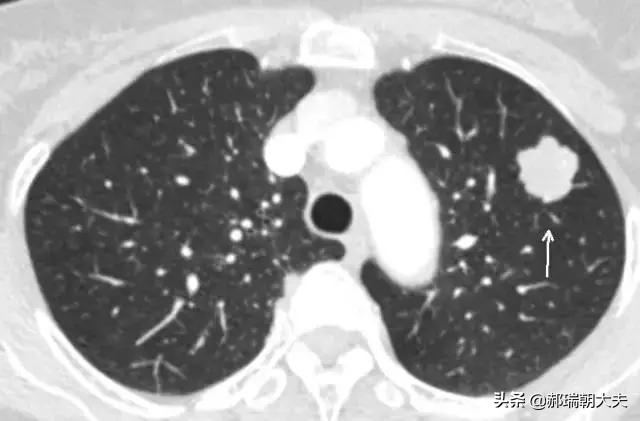

多発性肺結節と孤立性肺結節があり、多発性肺結節は結核やじん肺に続発することが多く、いずれも典型的な病歴や左葉の病歴で診断しやすい。我々が一般的に論じる結節は孤立性肺結節を指す。

健康診断への意識が高まるにつれ、肺結節が発見される人が増えている。肺結節とは画像診断の用語で、肺結節の画像上の定義は、肺実質に完全に囲まれた、境界明瞭な小さな病変(直径≤30mm).結節の形態は、固結または亜固結に分類される。亜固結はさらに、純粋なすりガラス結節と部分的な固結に分類される。直径30mmを超える病変は結節ではなく腫瘤であり、悪性の可能性が高い。

現在受け入れられている肺結節の定義は、直径3cm以下の限局性、円形、高密度、固形または亜固形の肺影である。 近年、低線量CTによるスクリーニングを受ける人口が増加するにつれて、孤立性肺結節に加えて多発性肺結節が検出される割合がかなり増加している。多発性肺結節は多くの場合、1個の肺結節と1個以上の小結節として現れる。多発性肺結節は2個以上の病変として定義される。多発性肺結節を有する患者は、外科的に確認され、臨床的に重大な注意を要する早期肺癌または前癌病変の複数の発生源を有する可能性がある。

病変の数によって、肺結節は孤立性肺結節、多発性肺結節、びまん性肺結節に分類される。